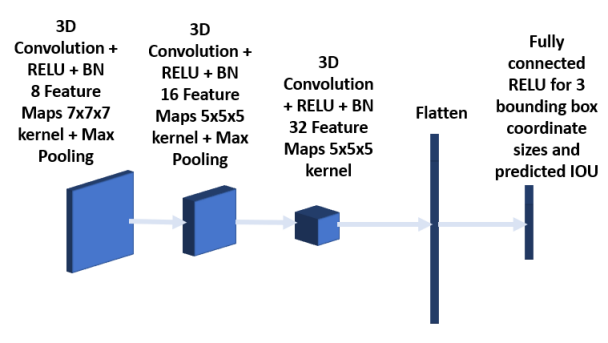

The bounding box network shown in Figure 6 is trained to predict the three coordinate sizes of the ROI. As the pre-selected bounding box is navigated, the regions whose IOUs exceed a threshold level are stored, along with ground truth sizes for training the bounding box network. The predicted IOU from the bounding box network is used as a confidence level associated with the bounding box. This feature is used in bounding box fusion (3.2.6) and also in semi supervised learning for pseudo label selection. The bounding box network consists of three 3D convolution layers together with batch normalization and RELU activation. The kernel size of the first, second and third convolution layers are 7x7x7, 5x5x5 and 3x3x3 respectively. The convolution layers are followed first by a fully connected layer and then by a RELU layer for 3 coordinate sizes. The loss function used is mean square error.